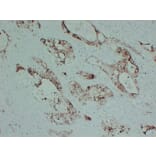

Immunohistochemistry - Anti-S100P Antibody [ABT-S100P] (A99686)

Immunohistochemical analysis of paraffin-embedded human Pancreatic carcinoma using Anti-S100P Antibody.